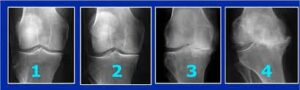

El diagnóstico de la artrosis de rodilla es sencillo. Se basa en el interrogatorio que realiza el médico al paciente sobre las características de los síntomas, seguido de una exploración de la articulación de la rodilla, con la evaluación de los movimientos de la misma.El diagnóstico se confirma mediante la práctica de una radiografía de las rodillas, en las que el médico puede ver los signos inconfundibles y característicos de la artrosis, como estrechamiento del espacio articular, cambios en el hueso y la formación de espolones óseos (osteofitos)..